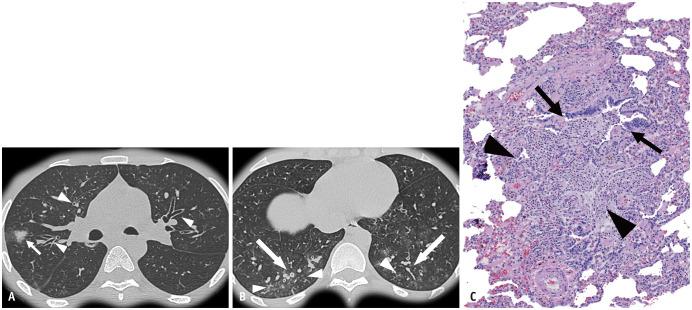

Non-infectious granulomatous lung disease represents a diverse group of disorders characterized by pulmonary opacities associated with granulomatous inflammation, a relatively nonspecific finding commonly encountered by pathologists. Some lesions may present a diagnostic challenge because of nonspecific imaging features; however, recognition of the various imaging manifestations of these disorders in conjunction with patients' clinical history, such as age, symptom onset and duration, immune status, and presence of asthma or cutaneous lesions, is imperative for narrowing the differential diagnosis and determining appropriate management of this rare group of disorders. In this pictorial review, we describe the pathologic findings of various non-infectious granulomatous lung diseases as well as the radiologic features and high-resolution computed tomography imaging features.